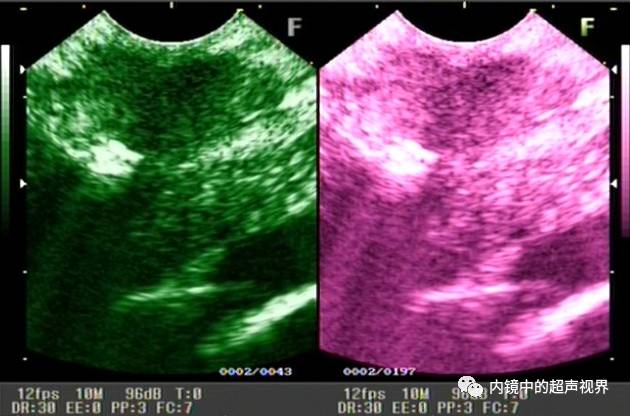

再来一纵隔肿物的图片,是DR30和80的对比,很明显。

纵隔肿物